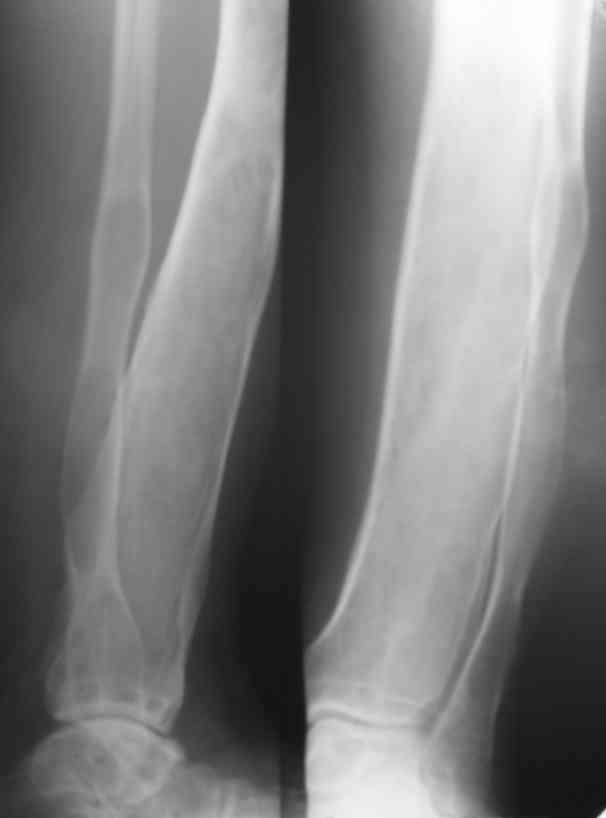

Я поддерживаю мнение доктора Odessky Jacob, что это образоавние возможно фиброзная дисплазия. Случай из моей практики - смотри рентгенснимки во вложении. Правда у моего пациента -полиосальная форма и болезнь проявилась в раннем детстве.

По представленным снимкам наиболее вероятен диагноз "фиброзная дисплазия".